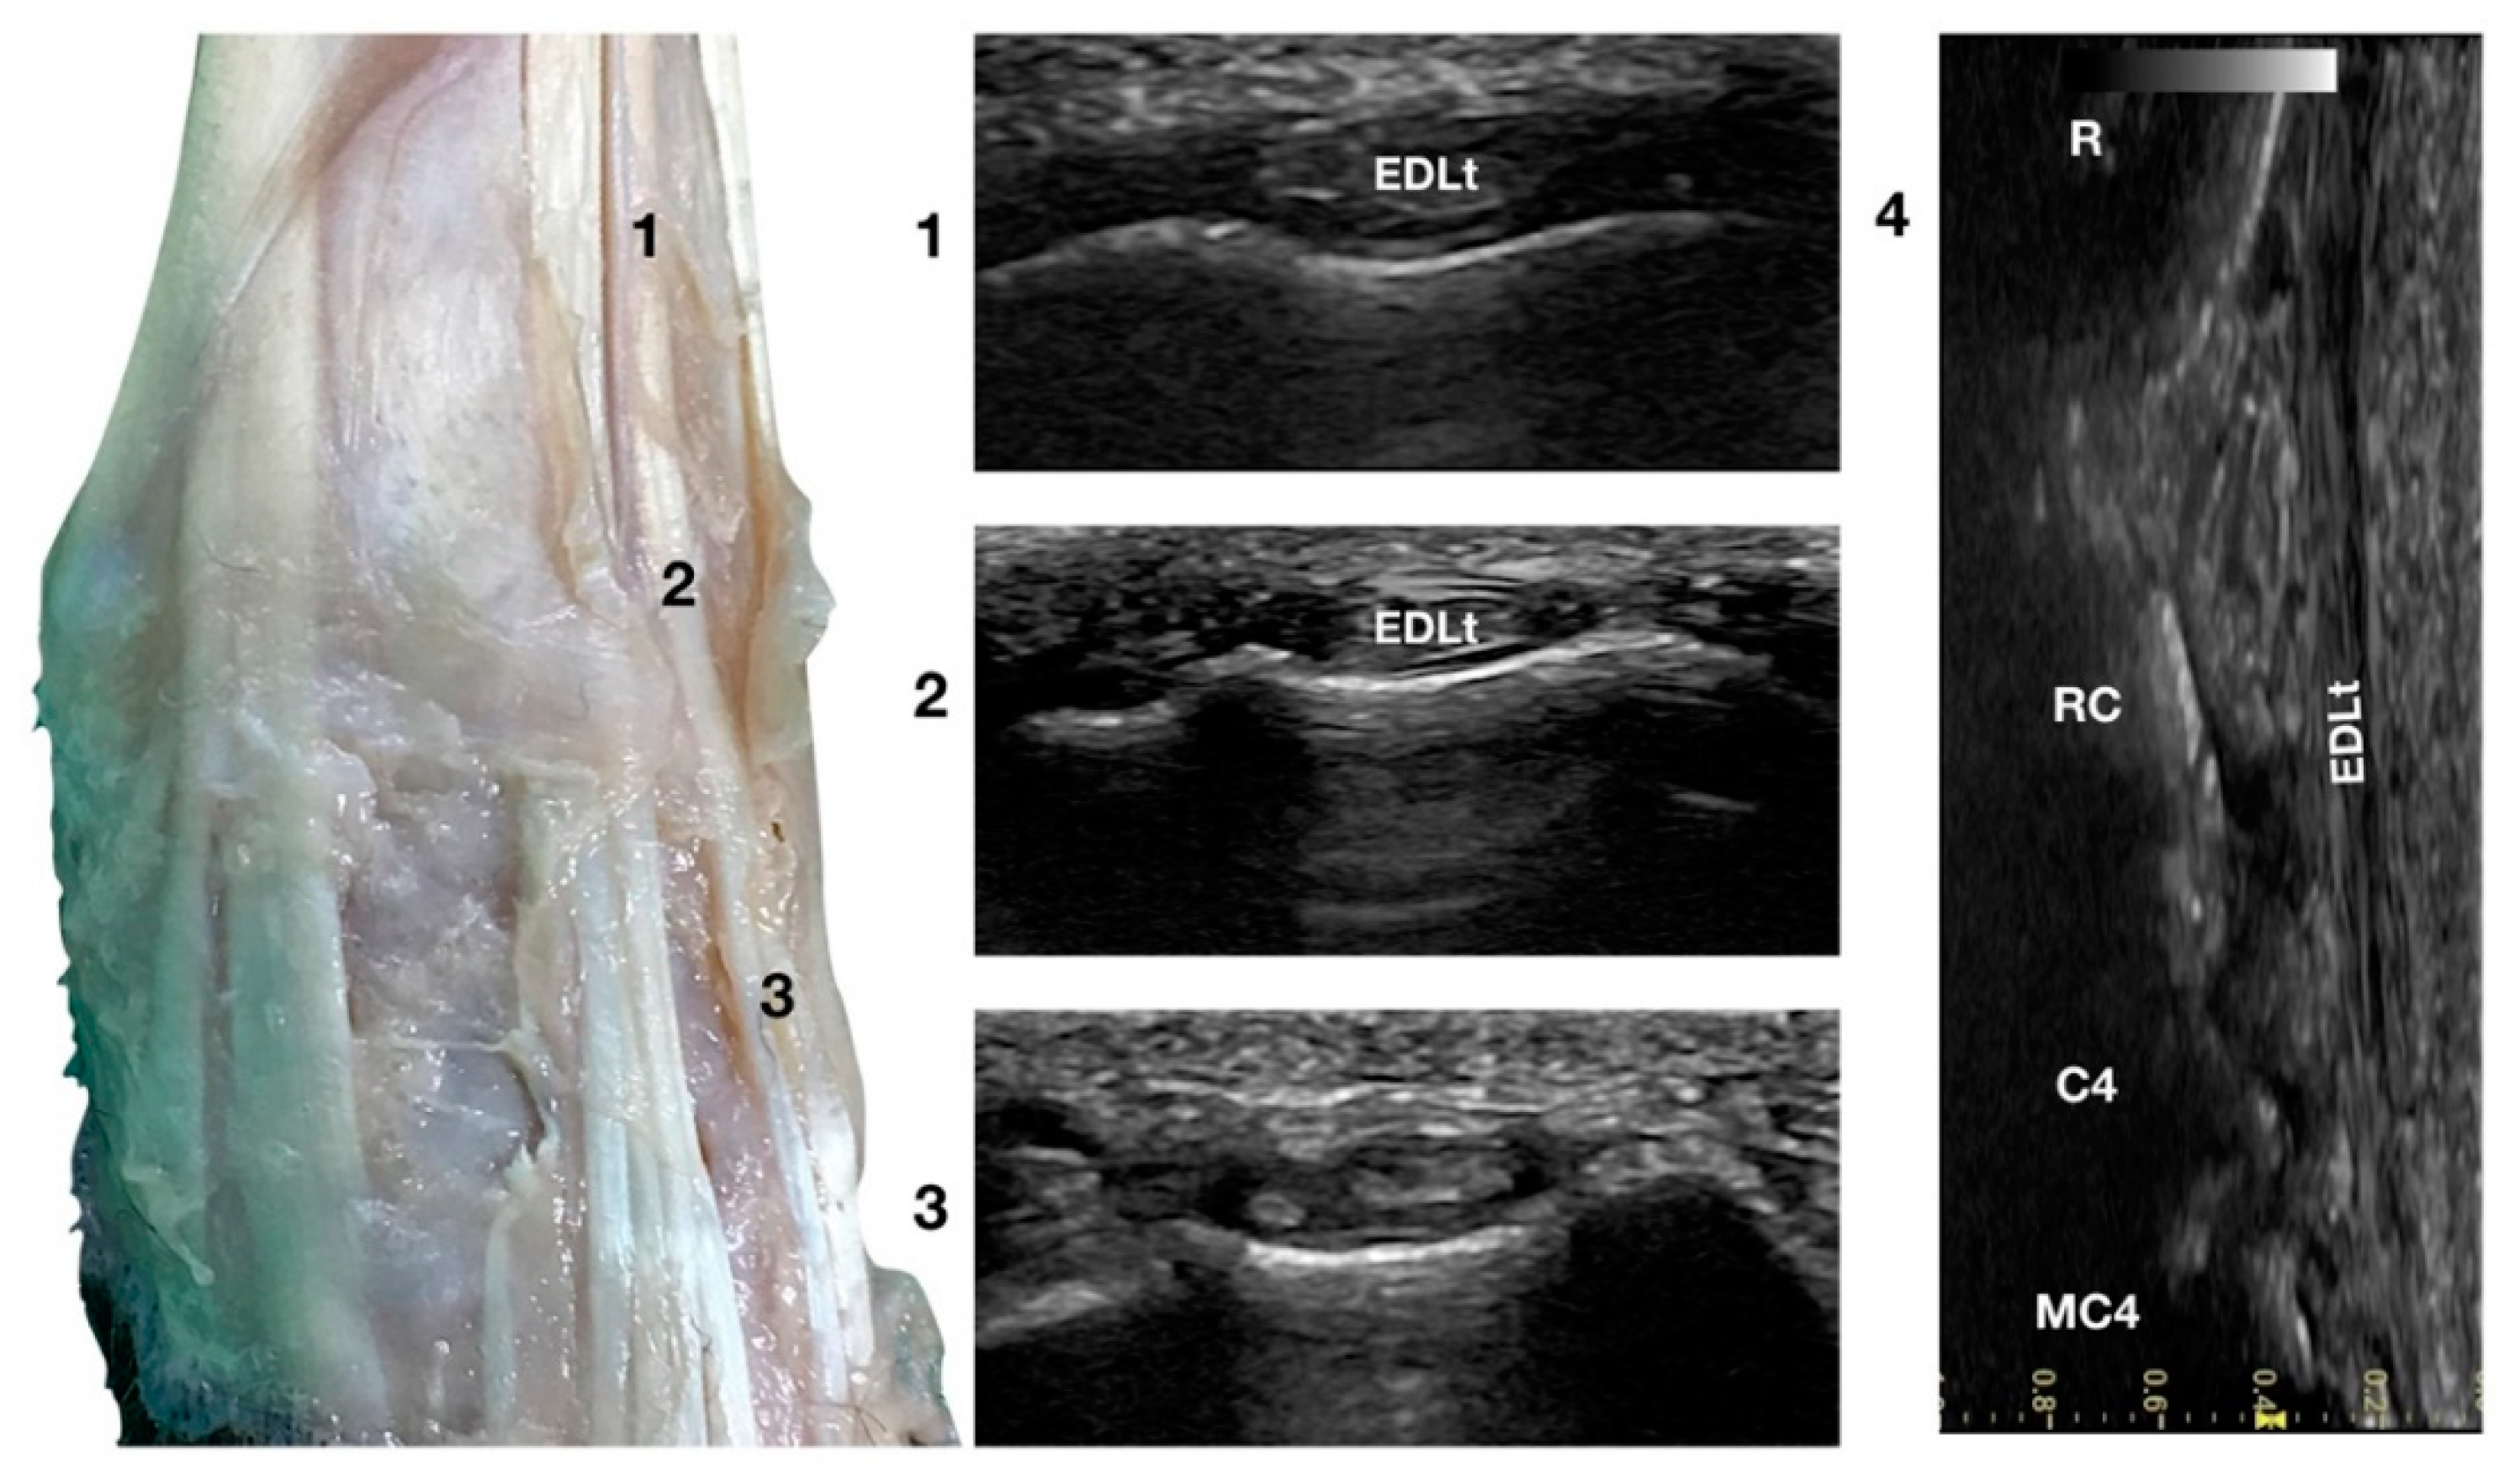

Just lateral to the EDCt at the ulnar notch of the radius, on a transverse scan, the Extensor Digitorum Lateralis tendon (EDLt) was seen as a small, oval to slightly rounded shaped structure (Figure 1a). It was more dorsomedially located than the more prominent Extensor Carpi Ulnaris tendon (ECUt), easily palpated on the lateral face of the carpus. It was the only tendinous structure lateral to the EDCt and medial to the ECUt. Proximally, the tendon maintained the same size and shape until the tenomuscular junction. Distally, at the intercarpal joint level, the homogeneous echogenicity of the tendon was interrupted by an oblique hyperechoic line that demarcated the two components arising from the united tendon (Figure 4).

Figure 4.

Dorsal carpal face centred on the Extensor Digitorum Lateralis tendon. At the ulnar notch level (2), the EDLt is seen as a thin oval tendon embedded in the deep Extensor Lateralis groove. Proximally (1), the tendon is thicker. The EDLt divides into two parts distally at the intercarpal joint (3). On the longitudinal scan plane (4), the fine fibrillar pattern of the thin medial tendon is visible. The bony surface beneath is recognisable. R, radius; RC, radiocarpal bone; C4, carpal bone four; MC4, fourth metacarpal bone.

The two parts of the EDLt passed through the groove between the distal ends of the radius and the ulna, over the dorsolateral border of the carpus to the metacarpus, and then diverged from each other. The two thin tendons (the medial is the smaller) passed over the dorsolateral surface of the corresponding metacarpal bones (third and fourth for the medial tendon, and the ulnar carpal bone for the lateral tendon). They ended on the dorsal surface to the distal phalanges of digits III, IV (the medial tendon divided into two branches), and V (the lateral branch). They were surrounded by a thick hyperechoic line (fibrous tendon sheath). The tendons, even if thin, were seen in the longitudinal scan until the mid-metacarpal diaphysis. It is possible that, in larger breed dogs, the tendon can be evaluated more distally. Elevating the foot from the ground and rotating the probe to check the longitudinal scan plane often helped in examining the distal portion. The extension and flexion of the lateral digits helped to better differentiate the tendon from the surrounding tissues and assess tendon function, lesions, adhesion, and subluxation.